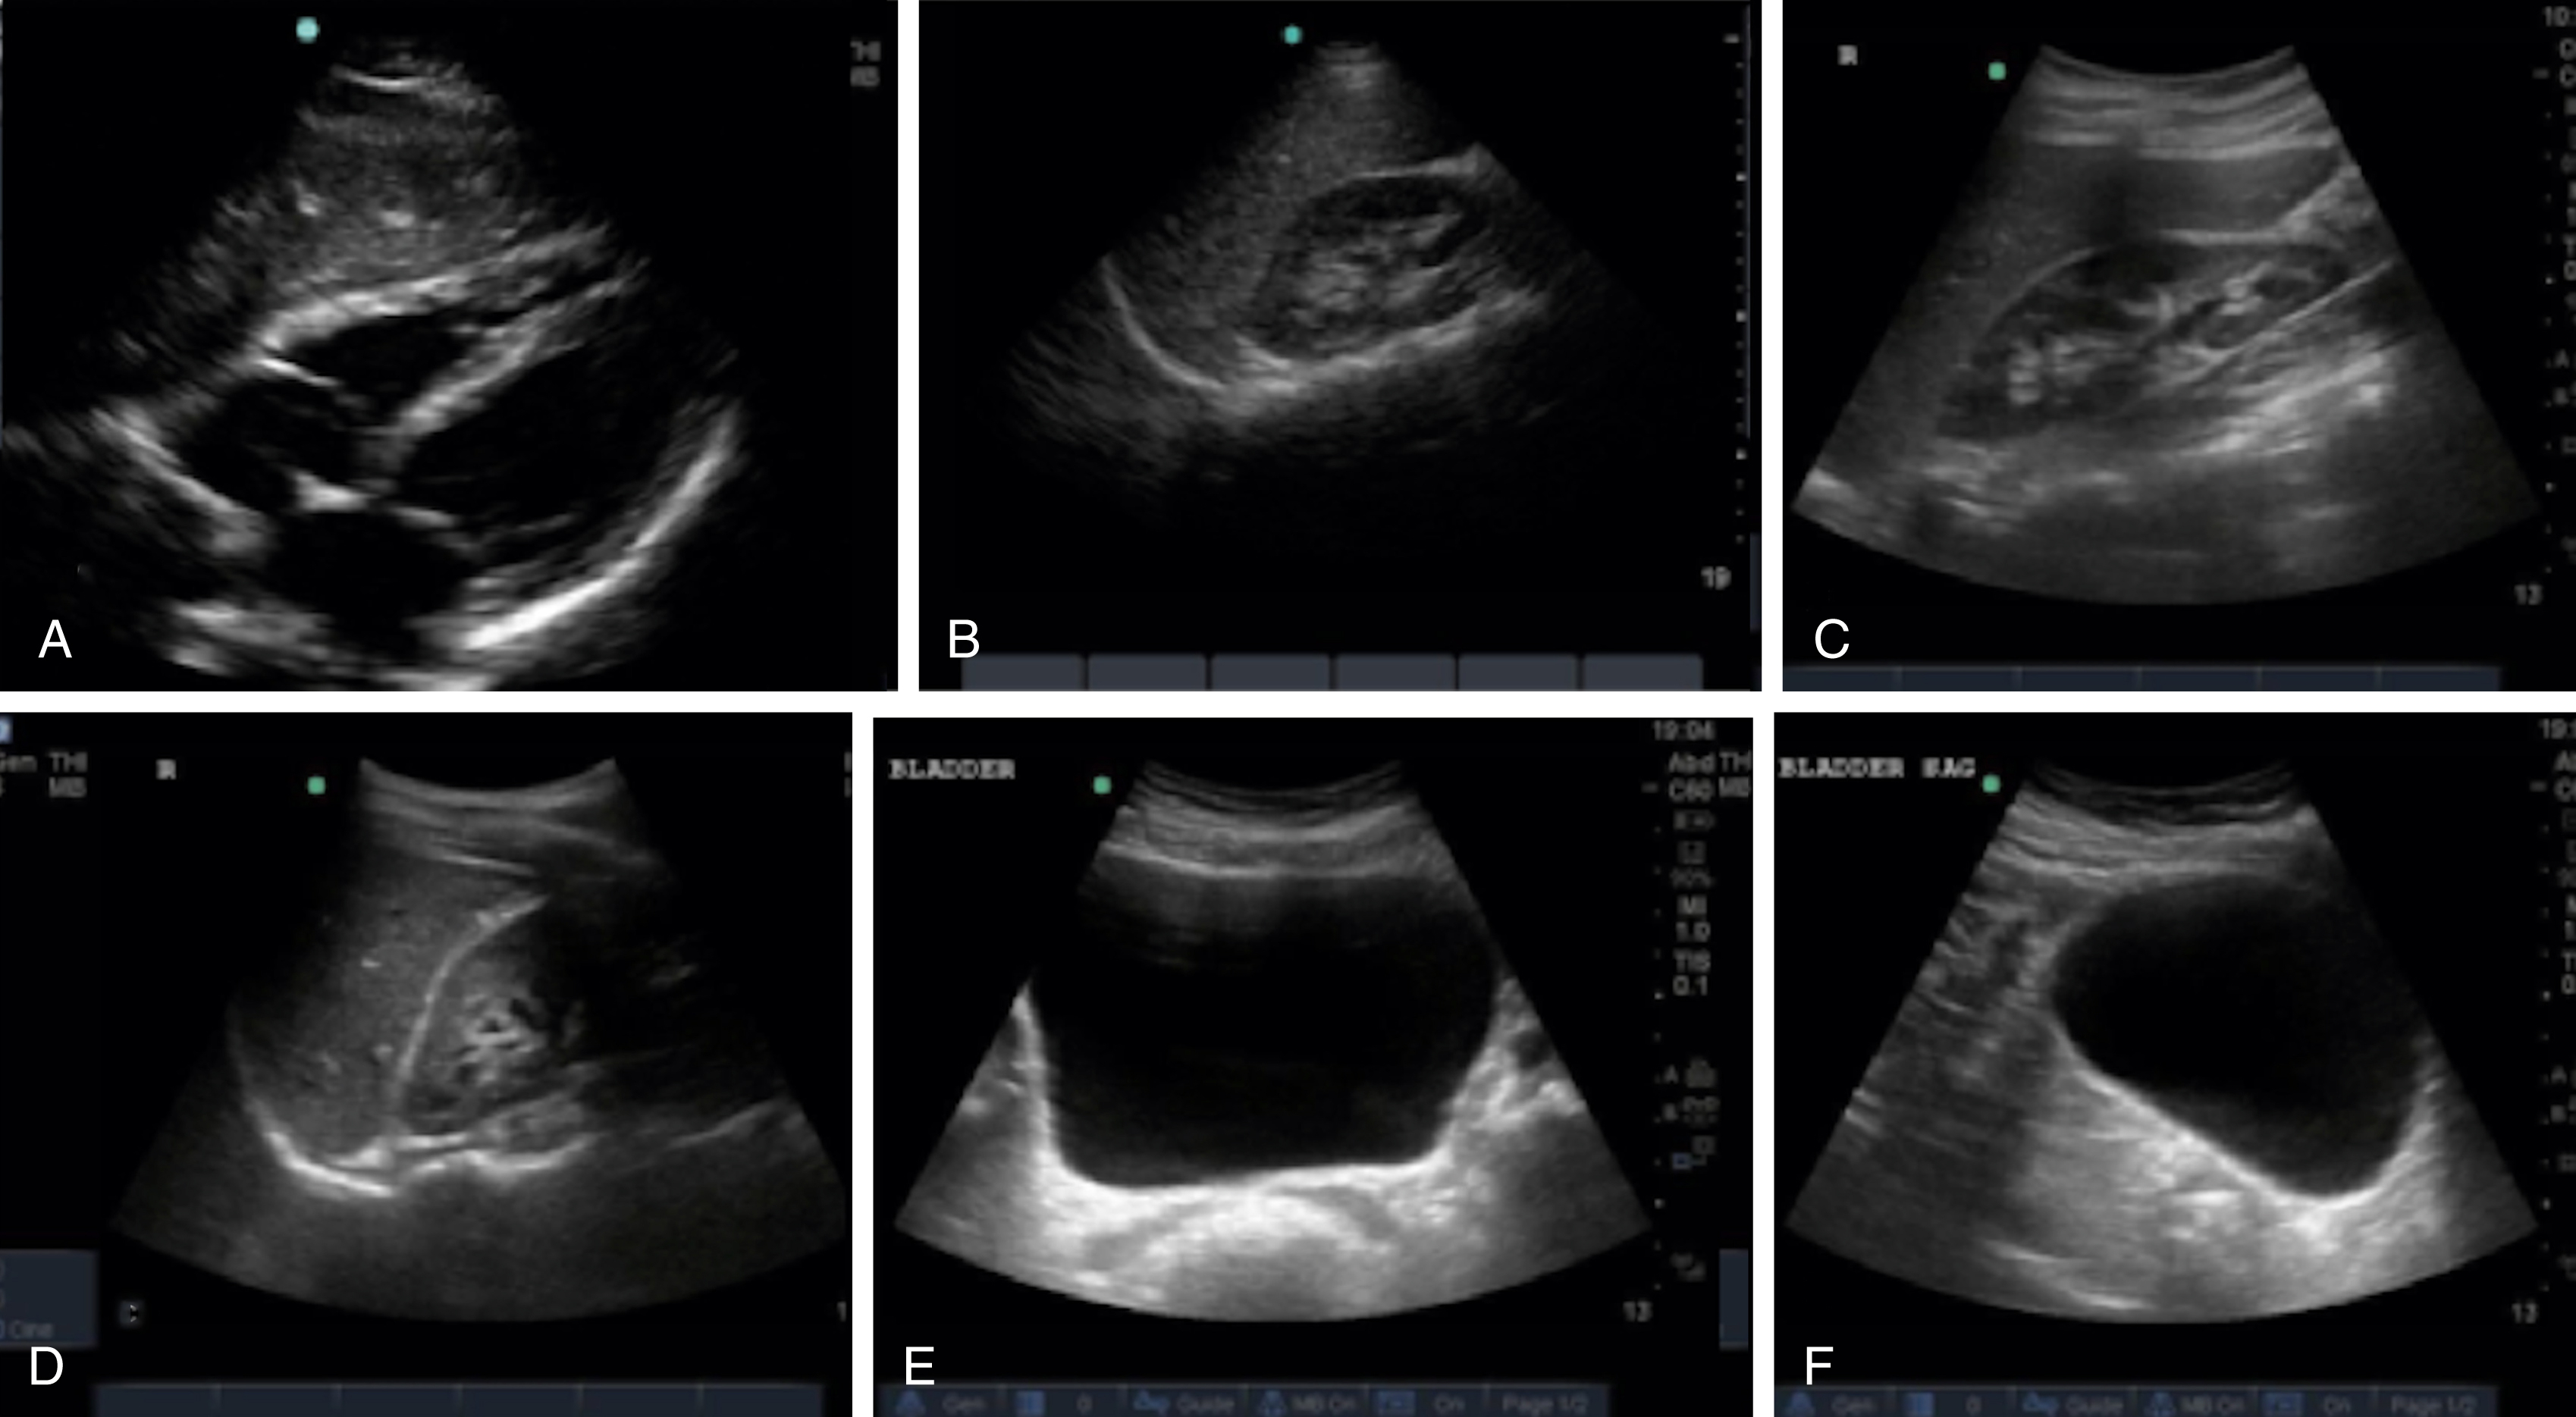

The FAST examination technique uses a low-frequency broadband transducer (2–6 MHz) to evaluate dependent peritoneal spaces, pleural spaces, and the pericardium for free fluid, which in the trauma patient is presumed to be blood. There are four main components of the basic FAST examination: (1) the right upper quadrant (RUQ) view, (2) the left upper quadrant (LUQ) view, (3) the pelvic view and (4) the cardiac view ( Fig. e3.1 ). The E-FAST includes anterior chest views to evaluate for pneumothorax. The RUQ view evaluates for fluid in the thorax (above the diaphragm) ( Video e3.1 ), hepatorenal space (Morison pouch) and the paracolic gutter (inferior edge of the liver and right kidney) ( Video e3.2 ), moving cephalad to caudad. The LUQ view, found slightly more superior and posterior than the RUQ, should mimic the RUQ views, but also include the subdiaphragmatic space, because free intraperitoneal fluid tends to accumulate here initially. The pelvis should be evaluated in the transverse and longitudinal planes, where fluid may be detected deep to the uterus (in females) or in the retrovesical space (in males) ( Video e3.3 ). The cardiac evaluation can be performed in either the subcostal (or subxiphoid) or parasternal window ( Video e3.4 ). Evaluation for pneumothorax uses a low or high-frequency transducer at a shallow depth, placed along the anterior chest wall and will be discussed in more detail in subsequent sections.

Negative FAST images. (A) Subxiphoid view with no pericardial effusion. (B) Negative RUQ view showing the thorax and hepatorenal space without the paracolic gutter visualized. There is mirroring and loss of the spine, indicating a negative thorax. (C) Negative paracolic gutter area by the liver tip in the RUQ view. (D) LUQ view showing negative thorax, as in B, and splenorenal space. (E) Negative transverse bladder view. (F) Negative sagittal bladder view.

Typically, free fluid is anechoic, but it can have echogenicity if active extravasation, a blood clot, or bowel contents are present within the fluid. Compared with other fluid-filled structures in the abdomen and pelvis, peritoneal free fluid generally has sharp pointed edges and an irregular shape, whereas most visceral or vascular structures have intrinsically smooth oval or round contours. The volume of fluid required for a positive US study depends on the site of injury, sonographic window, and experience of the operator, but 250 mL or more is generally visible, and nearly 600 mL of fluid is required for a positive upper quadrant window. With pericardial fluid, once a certain volume is reached, the pressure in the pericardial space increases dramatically, resulting in cardiac tamponade. Generally, at least 50 mL of fluid is required to cause hemodynamic compromise in a patient without prior pericardial inflammation ( Fig. e3.2 ).

Positive FAST images. (A) Positive RUQ view showing a thin stripe of fluid in the hepatorenal space. The thorax is negative and paracolic gutter not visualized. (B) Positive LUQ view showing a hemothorax and splenorenal space. There is loss of mirroring and continuation of the spine. (C) Subxiphoid view showing a pericardial effusion circumferentially. (D) Positive transverse bladder view with free fluid noted posterior to the bladder on the right of the image.